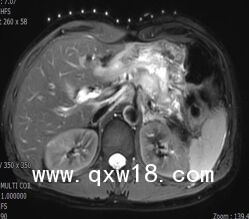

醫(yī)學(xué)圖像體外定位貼(MK#MR型,MR引導(dǎo)定位柵)產(chǎn)品說明:

【適用范圍】

MR引導(dǎo)下介入穿刺活檢或治療

【突出優(yōu)點(diǎn)】

為開展磁共振引導(dǎo)下穿刺活檢和消融介入治療創(chuàng)造了快捷定位條件??芍貜?fù)使用,全球獨(dú)有,多序列成像,標(biāo)記清晰。

【產(chǎn)品規(guī)格】

19cm×20cm,1套裝。